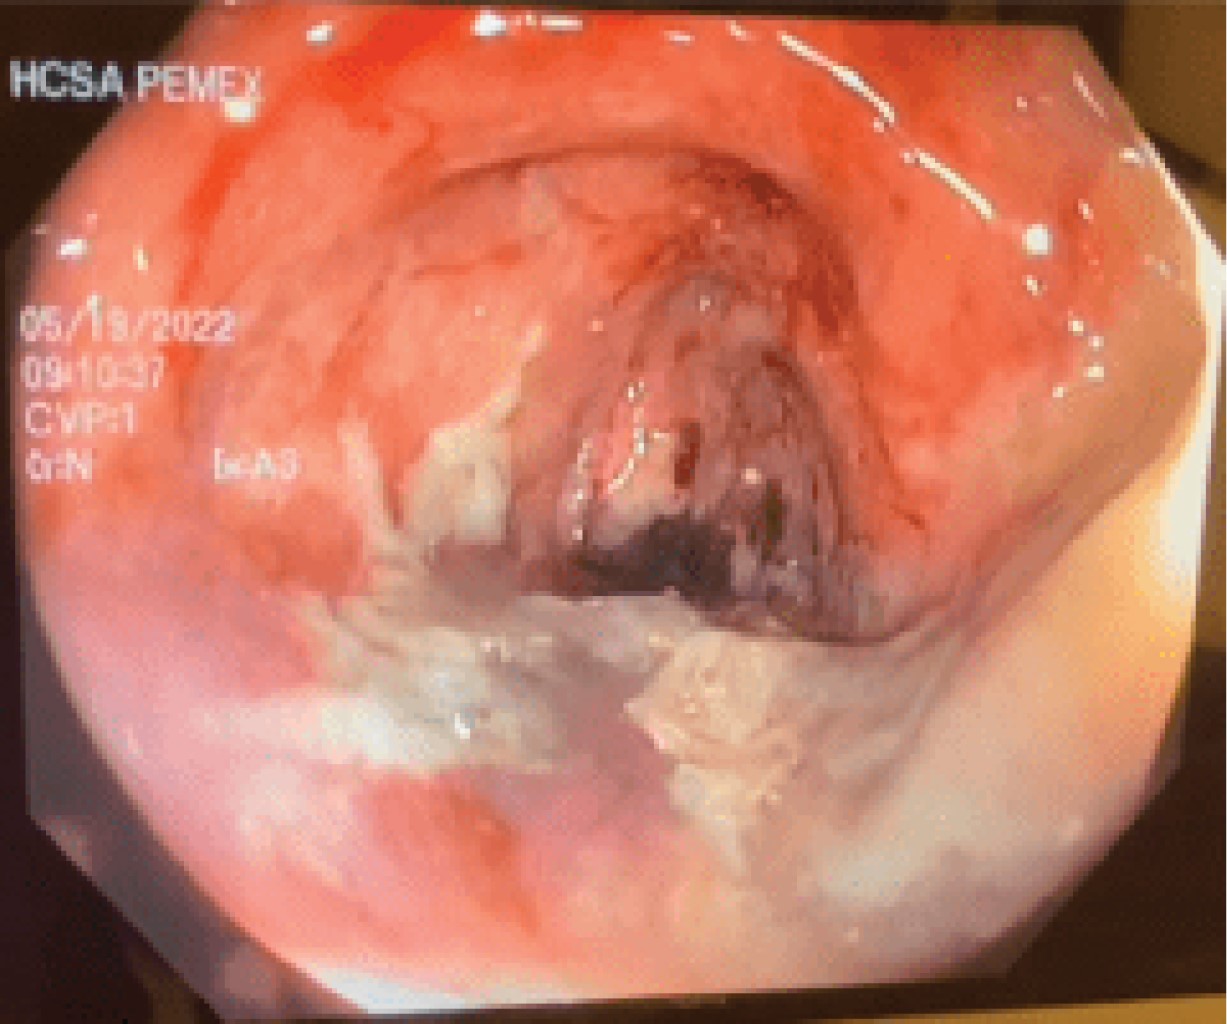

Figure 4